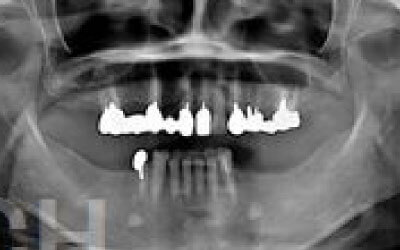

CTを使うことで、骨や歯の状態を3Dで確認でき、正確な距離測定も行えます。

骨の厚さや傾き、神経の位置などを事前にしっかりと計測することで、安全にインプラント治療を行うことができます。

インプラント治療では、顎の骨内に通っている神経を傷つけるリスクがあります。

しかし、事前にCTを撮影し、三次元的に神経までの距離を計測して治療計画を立てれば、心配することはありません。

また、過剰に削らないようにストッパーも使用しているため、安全に治療が進められます。